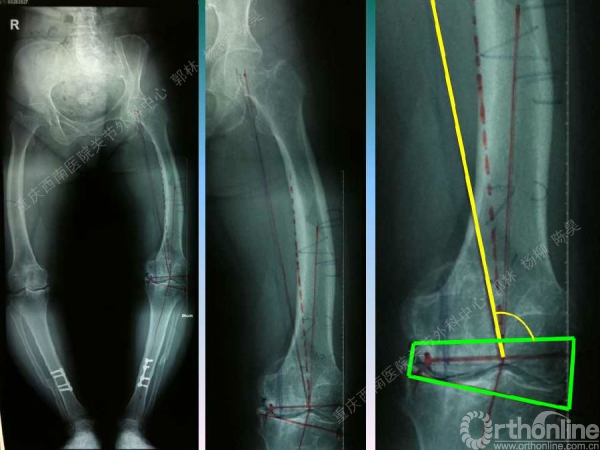

导读:文中,来自重庆西南医院的郭林教授为大家介绍了股骨冠状位关节外畸形的TKA的相关知识,并详细阐述了关节外畸形的概念、诊断、关节内滑移截骨技术等相关内容。

滑移截骨纠正关节外畸形